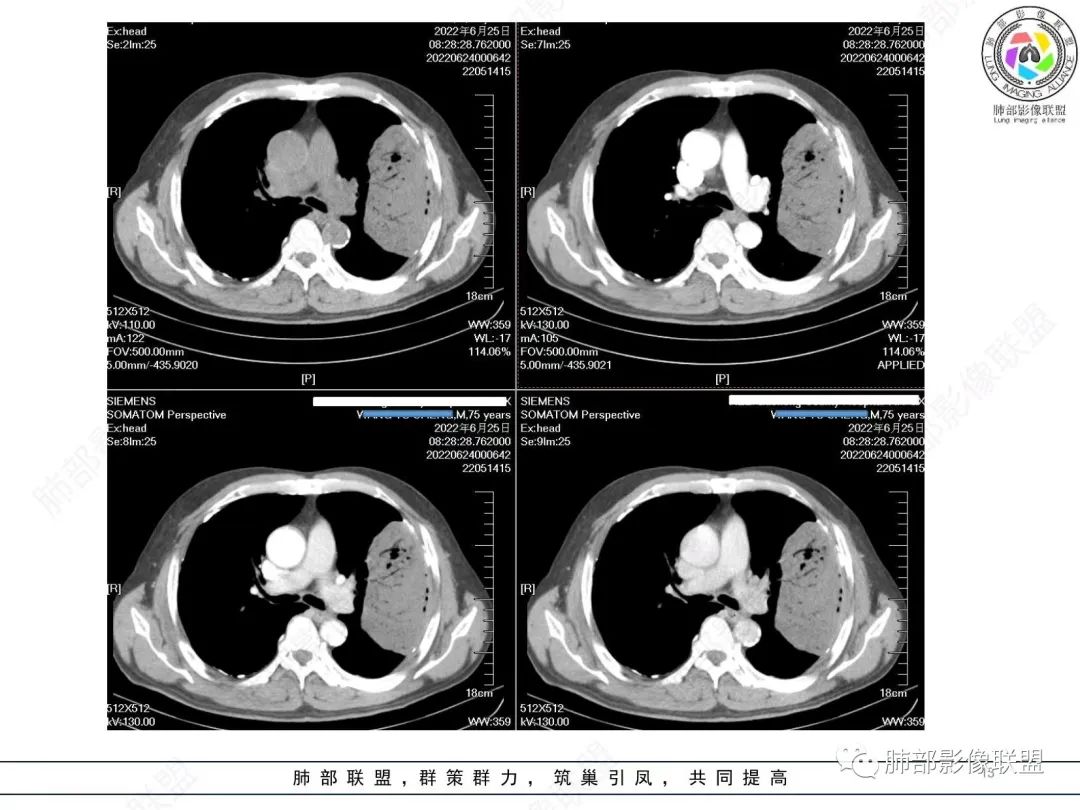

原发性肺肉瘤样癌(PSC)一组临床罕见的肺部肿瘤,属于上皮细胞源性肿瘤,仅占肺部恶性肿瘤的0.3%~4.7%。为含有肉瘤形态细胞或肉瘤样分化的非小细胞肺癌,癌成分多为鳞癌或腺癌,肉瘤成分最常见的是纤维肉瘤。

肺肉瘤样癌的CT表现主要特点:

1)部位:周围型或中央型软组织肿块,以周围型为多见,且肿瘤多位于肺上叶。如本例:该肿瘤位于左肺上叶。

2)大小及形态:由于本病恶性程度高,早期症状不明显,发现时肿块均较大。如本例病变巨大。

3)肿块边界和边缘:多较清楚,呈圆形、类圆形,且由于肿块生长速度不均匀,可见分叶,毛刺少见。有报道肿块周围毛玻璃影是多形性癌特征表现。

4)密度:肿块平扫为软组织密度,由于体积较大,内部常见大片状坏死,可出现不规则厚壁空洞或坏死内多发无壁小空洞,坏死多不均匀:坏死灶内可见如柳絮样的斑片样强化灶,坏死边缘与非坏死区分界不清本例坏死较明显,密度不均匀。

5)肿瘤强化方式:肺部恶性肿瘤强化程度与其血供丰富程度相关,血供丰富多强化明显,反之则较差。由于PSC 周边实性部分富血供及内部黏液变性、坏死,增强后肿块多数呈轻-中度边缘环形强化或不均匀小斑片状强化。国外学者对照病理发现肿瘤细胞或胶原组织增强扫描时强化,无强化的低密度区代表了黏液样变性区和出血坏死区。